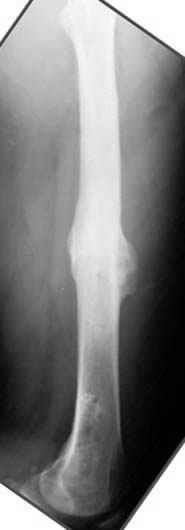

На рисунке N1 предоперационный план лечения ложного сустава шейки бедра- линия ложного сустава, угол и направление введения импланта, клиновидная остеотомия в градусах и миллиметрах, второй снимок после коррекции, расчет, на сколько удлиняется конечность и размеры импланта;

N3 рисунок окончательный снимок, после операции моя рентгенограмма должен выглядеть примерно как эта картина. На N4 снимке клин перед удалением; N5 послеоперации 3 нед.; N6 окончательная рентгенограмма.